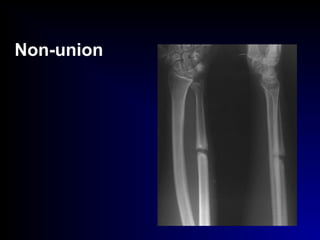

• Non-union :(pseudo-arthrosis)

ttt. : I.F. + B.G.

Non-union